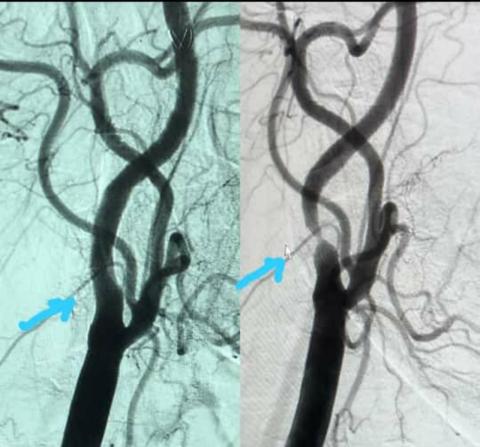

دبي، الإمارات العربية المتحدة، ("ايتوس واير"): توجهت السيدة آمنة إلى مستشفى الإمارات جميرا للحصول على الرعاية الطبية المتقدمة بإشراف خبراء، بعد معاناتها من ضعف البصر في عينها اليمنى لعدة أسابيع. واستقبل مستشفى الإمارات - جميرا، التابع لشركة الإمارات للرعاية الصحية، المنشأة الطبية ذات الشهرة العالمية، والذي يضم 100 سرير، ويمثل منارة التقدم في مجال الرعاية الصحية بالمنطقة، السيدة البالغة من العمر 43 عاماً والمصابة بالسكري أيضاً، وتم إحالتها على الفور إلى استشاري أمراض القلب والأوعية التداخلية، ليتم تشخيص حالتها بانسداد شديد في الشريان السباتي الأيمن، ما يعوق نقل الدم المحمل بالأكسجين إلى الدماغ. كما أظهرت بعدها تقييمات الخبراء في المستشفى انسداد شريان الرقبة الأيمن بنسبة 90 بالمائة.

بيد أن الدكتور علام القوتلي، رئيس قسم طب القلب والأوعية الدموية واستشاري أمراض القلب والأوعية التداخلي في مستشفى الإمارات - جميرا ، وبعد تقييمه لحالة المريضة، أوصى باللجوء إلى إجراء جراحي طفيف يتطلب تركيب انبوب معدني شبكي (دعامة) من نوع خاص في الشريان السباتي لإزالة الانسداد والحد من خطر الإصابة بالسكتة الدماغية في المستقبل القريب بدون إجراء جراحة كبرى.

وتم اعتماد الدعامة المختارة لهذه العمليات من قبل إدارة الغذاء والدواء الأمريكية ، ويتم تركيبها باستخدام التنظير الفلوري من خلال فتحة دقيقة في أعلى الفخذ وعبر أنبوب وسلك خاصين للمساعدة في فتح الشريان وتقليص فرصة تضييق الشريان مرة أخرى.

وتم إجراء العملية في مركز القسطرة القلبية والوعائية المتطور في مستشفى الإمارات جميرا، واستغرقت 30 دقيقة، وتكللت بنجاح كبير في إزالة الانسداد بدون أي مضاعفات. وتم إخراج المريضة من المستشفى إلى المنزل بعد أقل من 24 ساعة.